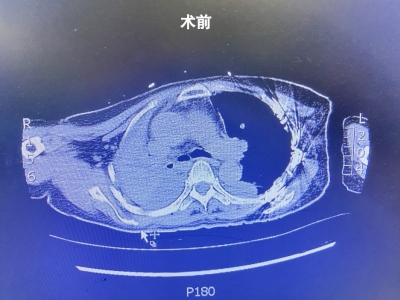

我院成功实施首例ECMO辅助下支气管断裂吻合术